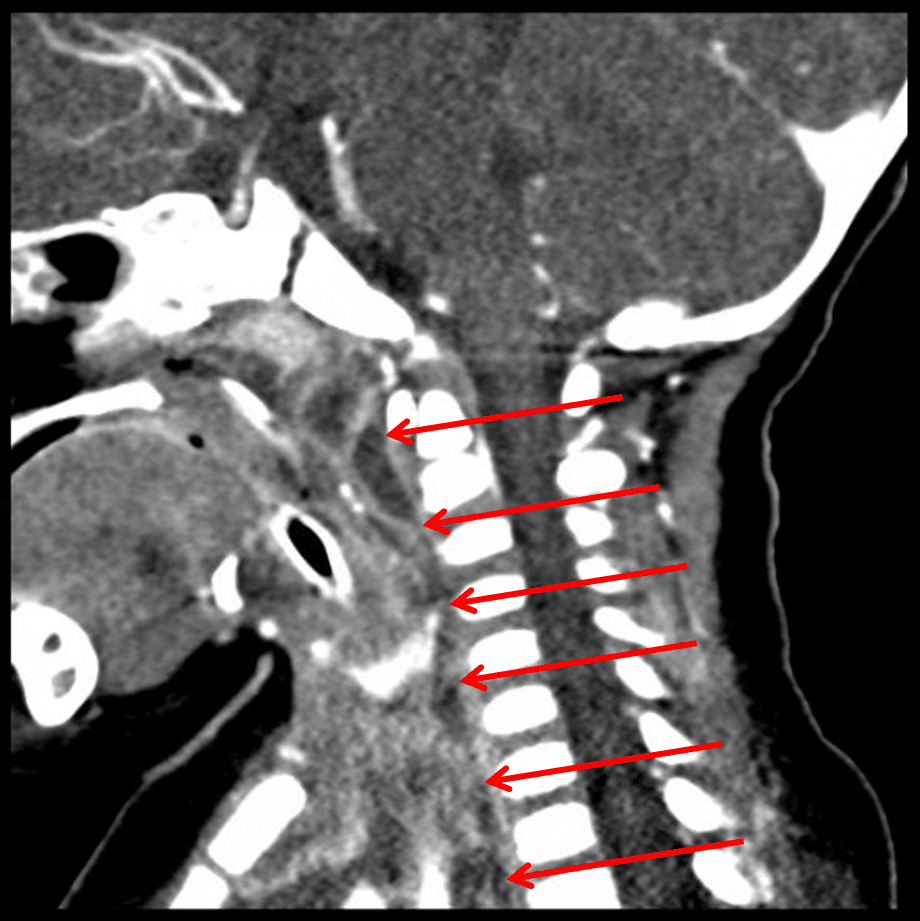

Red arrows: extension of infection through the retropharyngeal space.